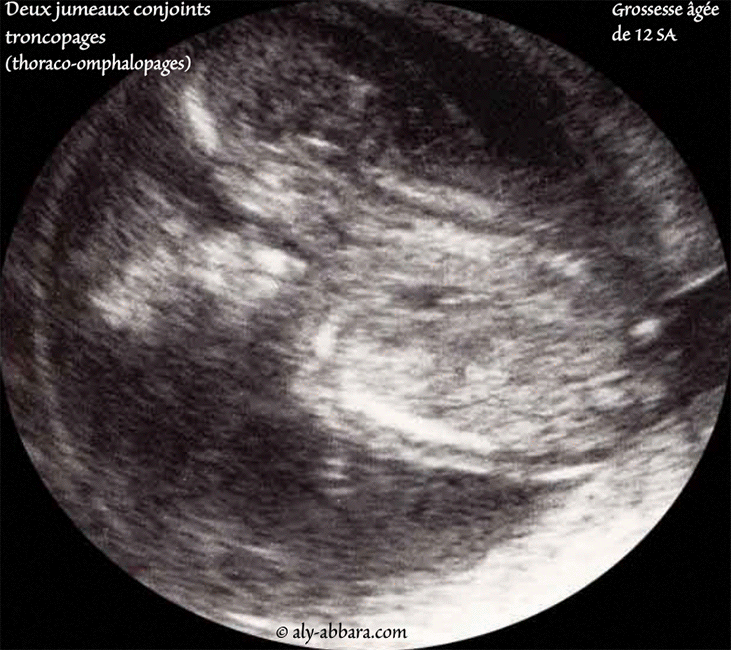

| Grossesse gémellaire âgée de 12 SA et composée de deux jumeaux conjoints thoracopages (thoraco-omphalopages) Il s'agit bien sûr d'une grossesse gémellaire vraie (monozygote), mono-amniotique monochoriale. |